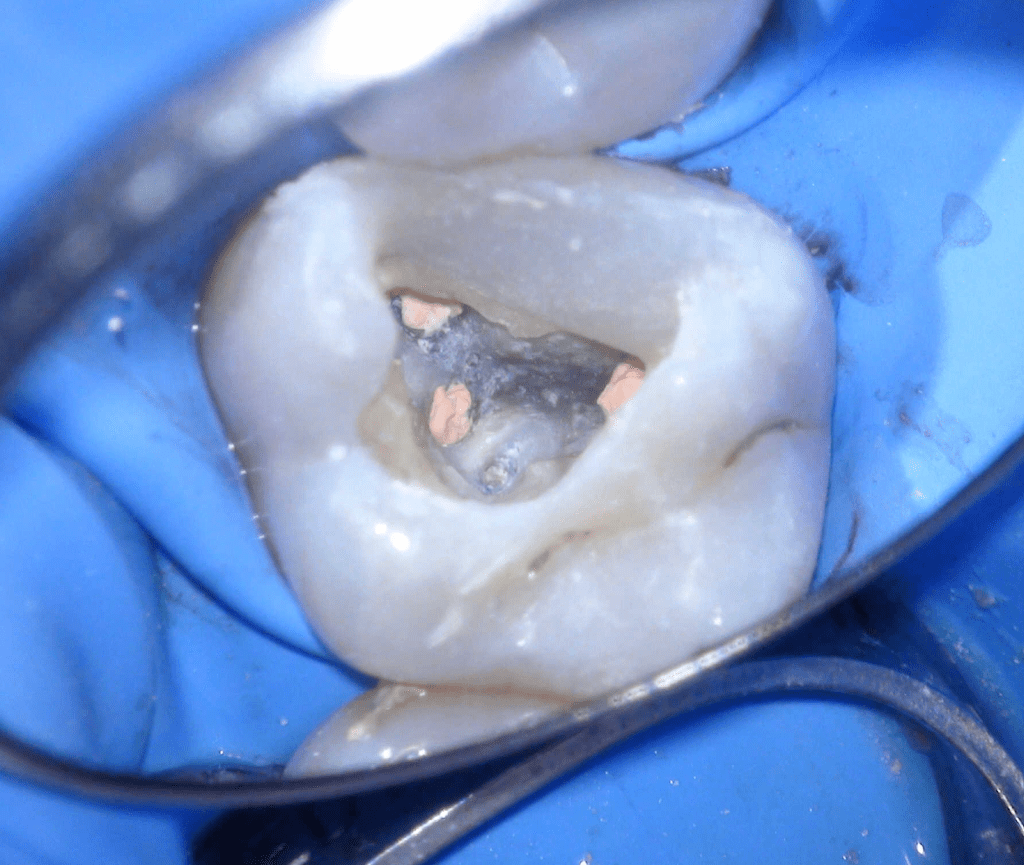

Fisura, remoción amalgama para explorar